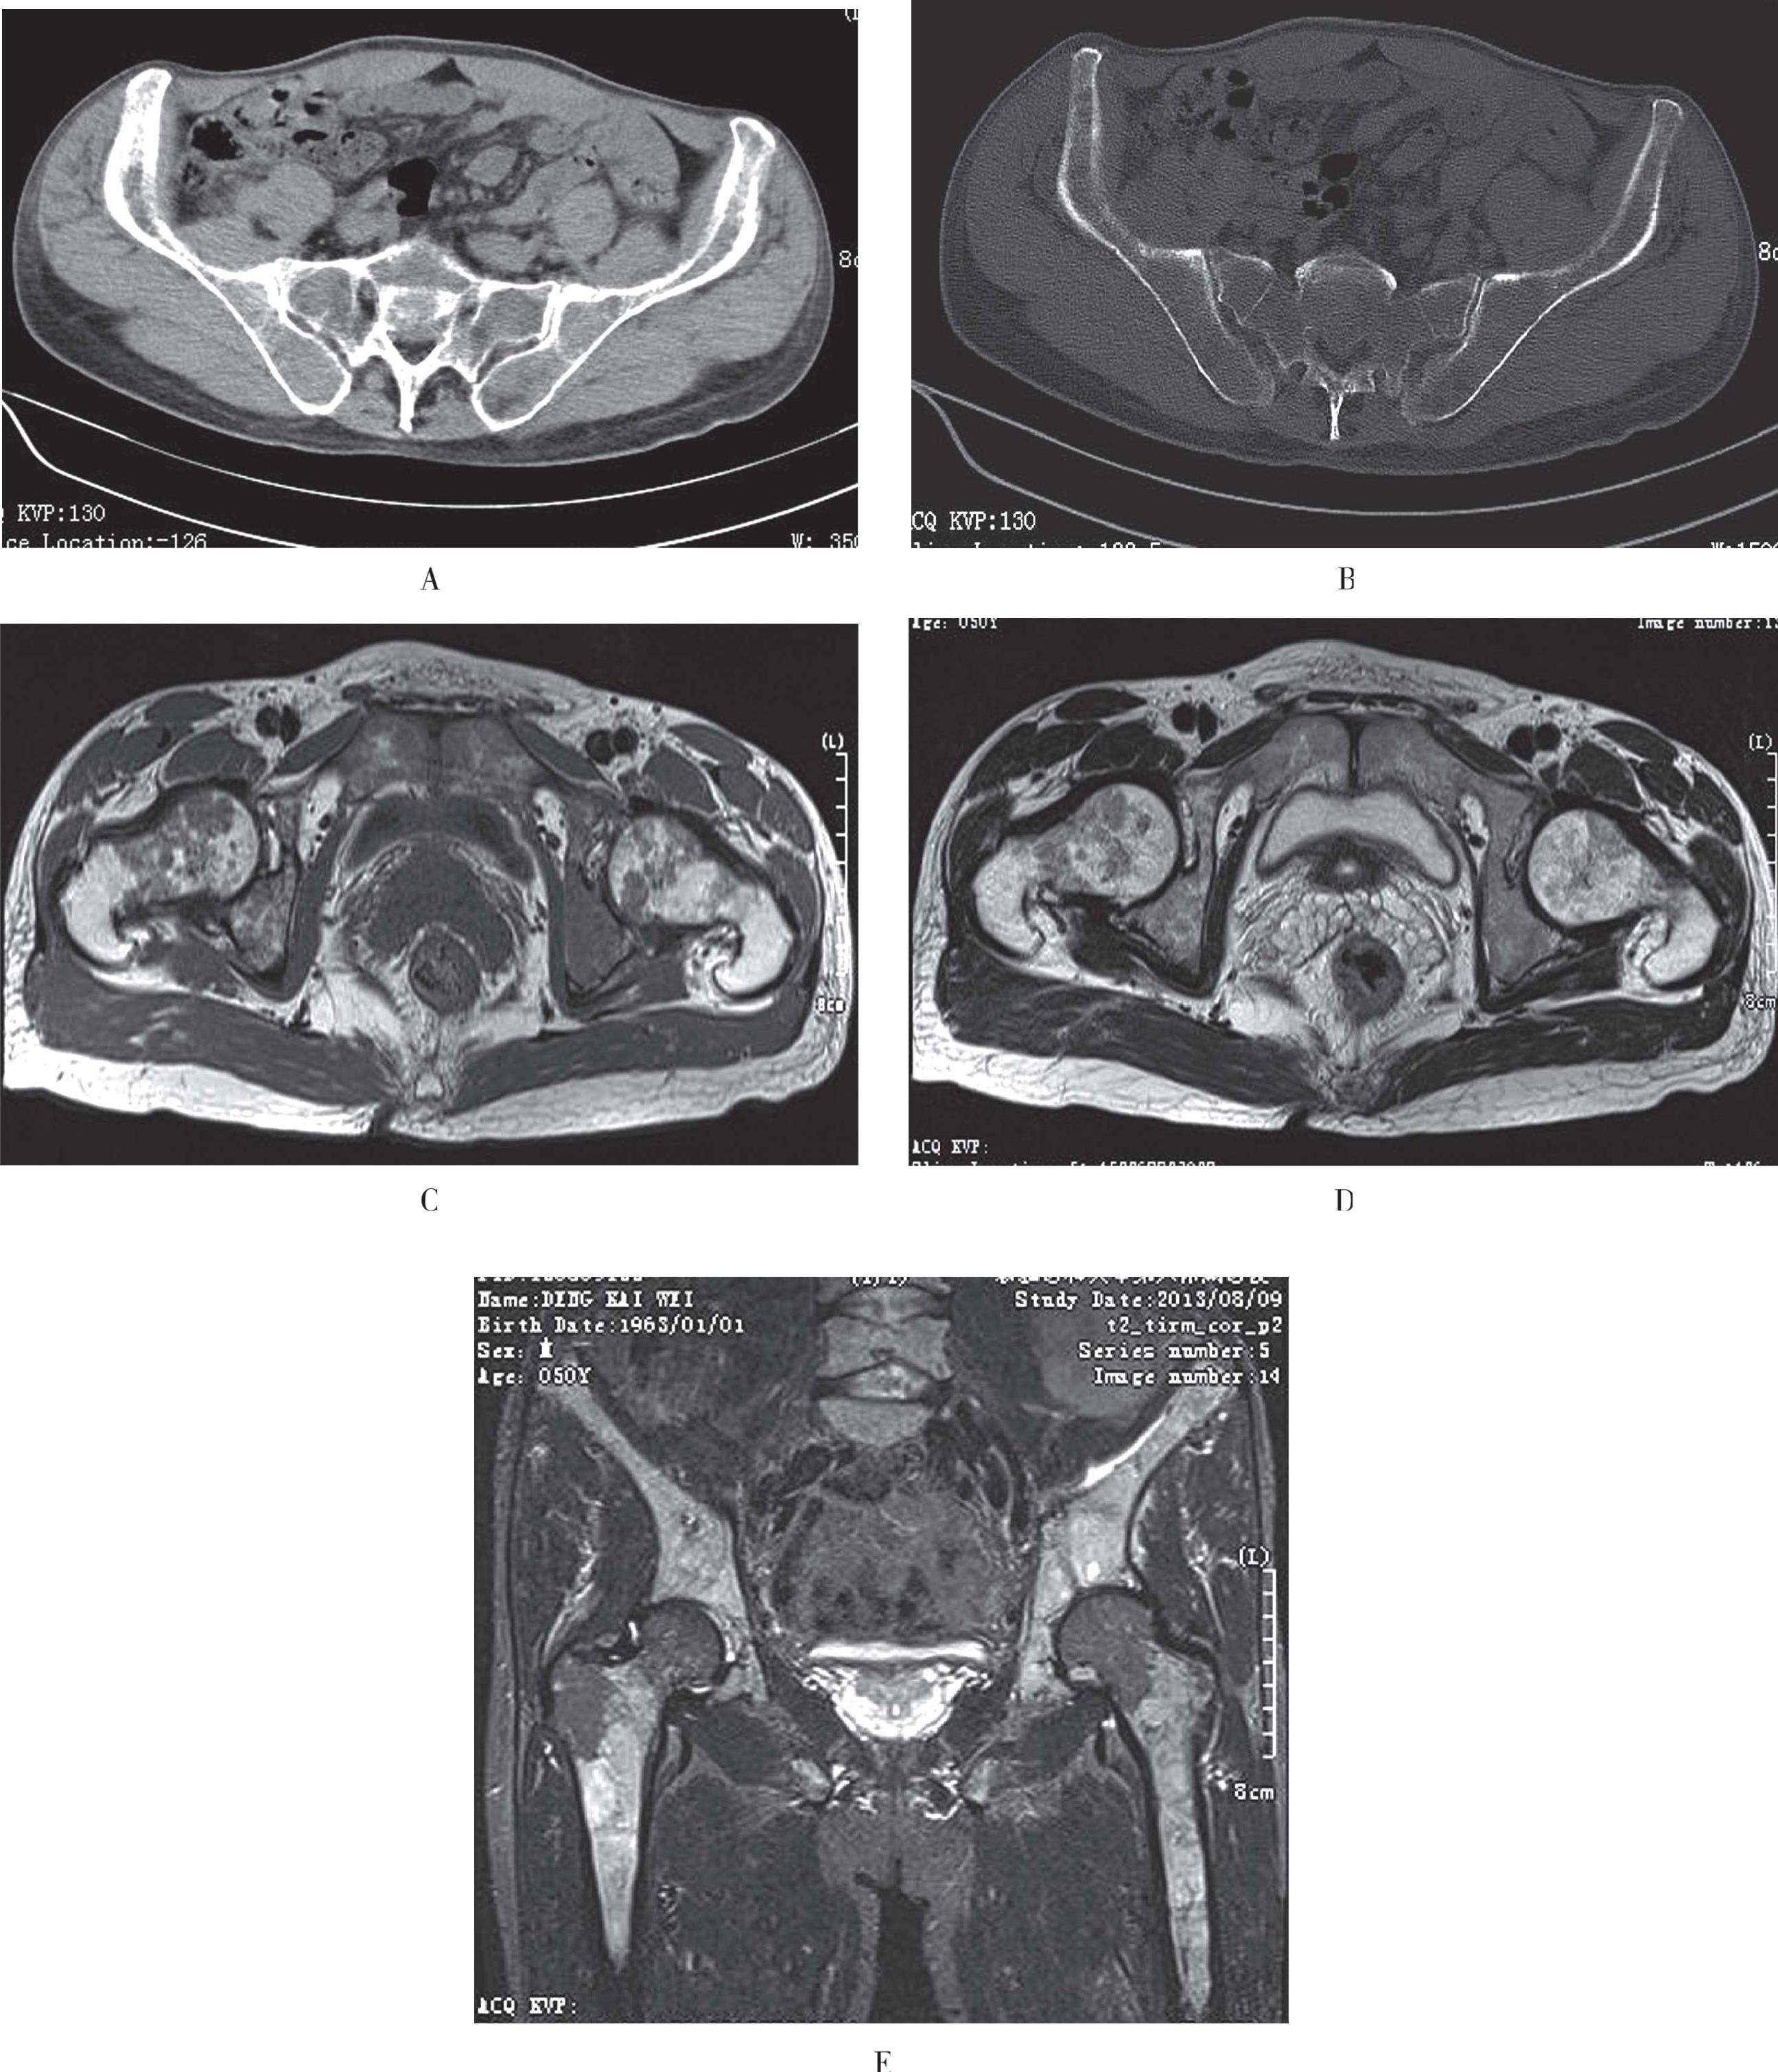

(2)CT表现椎体后部的溶骨性骨质破坏,骨皮质呈分叶状、花边状破坏,晚期出现椎体病理性压缩性骨折,常见于肺癌与乳腺癌转移。成骨型转移约占15%,常见于肝癌或甲状腺癌,混合性转移20%左右。对早期脊柱转移瘤的诊断,CT敏感性要远较MRI与核素扫描低(图3-54A、图3-54B)。

(3)MRI转移瘤T1WI表现为局灶性或弥漫性低信号,T2WI上根据成骨、溶骨的不同信号有所差异,溶骨型信号增高,增强后大多有强化。核素扫描目前认为是检测骨转移瘤效-价比最高的检查方法,能比X线片早18个月发现转移(图3-54C、图3-54D)。

A、B. CT清晰显示L 5 椎体内片状溶骨性骨质破坏区,并可见椎弓根受累及软组织肿块;C、D. T2WI上见腰骶椎多发稍低信号,呈跳跃状,L 5 椎体骨皮质不连续,压脂序列病变呈高信号,部分棘突受累

图3-54 脊柱转移瘤的影像学表现